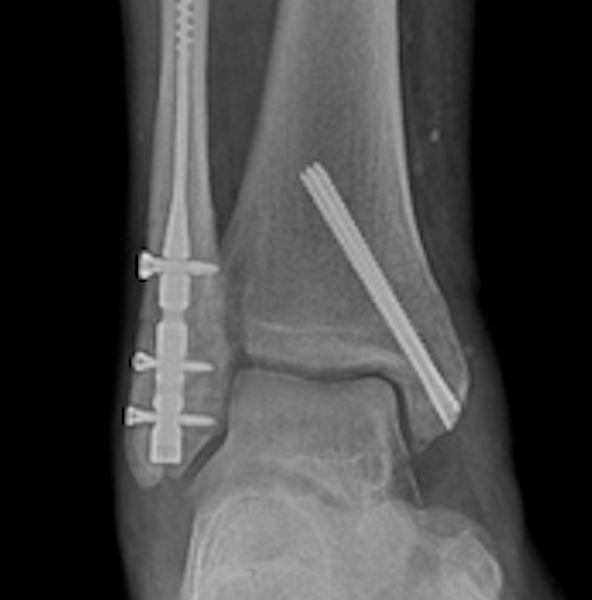

Standard Radiographs. Initial evaluation includes standard anteroposterior, lateral, and mortise radiographic views. Important findings to suggest tibiotalar joint instability include: talar shift or tilt, widened medial clear space (>4 mm or asymmetry compared with the contralateral clear space), fibular shortening or malrotation, and posterior malleolar displacement affecting joint congruency (Figure 1).